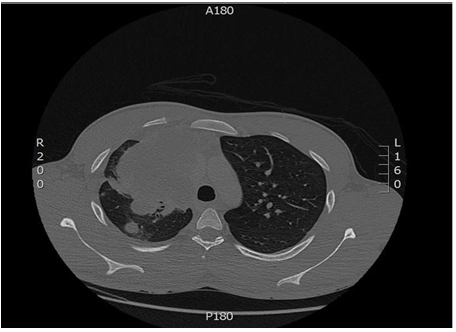

A 22-year-old male patient was referred to our hospital from outside hospital, as a case of germ cell tumor of lung origin according to report from there. He was a heavy smoker for last 10 years, presented there with cough most of the time, which was dry for 3 months, with dyspnea on lying down. The symptoms progressively increased with coughing small quantity of fresh blood with sputum associated with right chest pain with no fever. He was dyspnic, oxygen saturation was 92 to 94% on 10 L of oxygen, heart rate was 102 beats per minute with no lymphadenopathy, no lower limb edema. Chest with stony dullness to percussion noticed with decreased air entry on right side with no organmegaly. Testicular examination was normal with no significant mass. The initial laboratory assessment at that time showed normal complete blood count, and biochemistry. The tumor marker showed high beta-hCG, (more than 10,000 IU/ml) with normal alpha-fetoprotein. The CT chest showed large right side mediastinal mass, about 10x8x15 cm with adjacent compression of superior vena cava and right pulmonary artery with no evidence of invasion and also, there were multiple pulmonary nodules with small right side pleural effusion (Figure 1). Bronchoscopy was done, but the biopsy and BAL was negative for malignant cells. The BAL culture revealed the growth of Escherichia coli and started on antibiotics, according to sensitivity for 6 days, but with no clinically and radiologically improvement, so fine-needle aspiration (FNA) and a biopsy was done from mass and initial report showed it is a germ cell tumor, so the patient was referred to our hospital for further assessment.

Figure 1: Baseline computed tomography scan of chest with contrast.